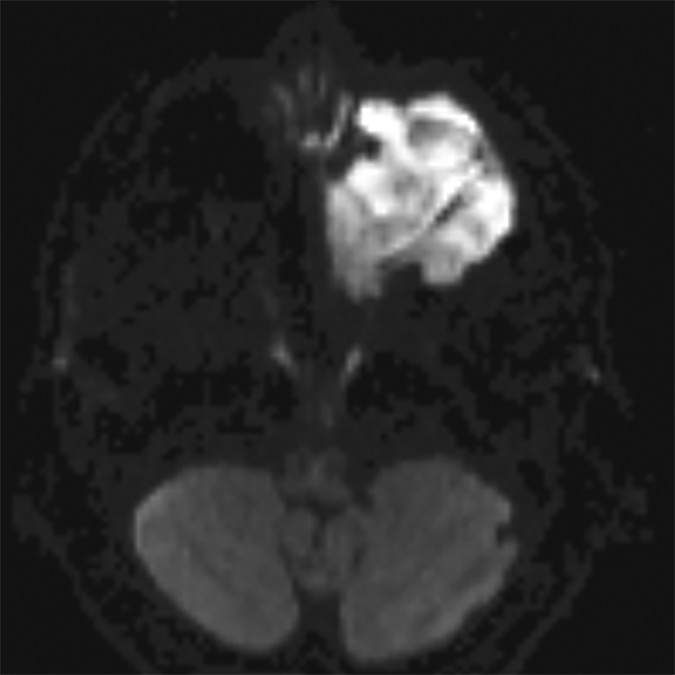

In certain instances, diffusion pulse sequences can offer a complementary adjunct to conventional MR pulse sequences, but neither diffusion-weighted imaging (DWI) or diffusion tensor imaging (DTI) should be utilized as a standalone technique for characterizing the benignity of head and neck lesions. Moreover, since mean apparent diffusion coefficients (ADC) values derived from DTI parameters are characteristically lower than ADC values developed from DWI parameters—frequently lower than reported malignant threshold values—the two should not be used interchangeably (Fig. 3).